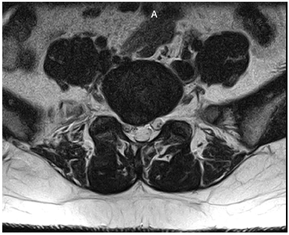

辅助检查:2022年07月20日腰椎MRI示L5/S1椎间盘变性并右后方脱出,S1右侧神经根中心区受压(图1,图2,图3,图4)。

患者慢性病程,反复发作并逐渐加重,以腰腿痛为主诉,无间歇性跛行,无夜间疼痛加重,无潮热盗汗,无二便障碍,完善腰椎MRI提示L5/S1椎间盘变性并右后方脱出、S1右侧神经根中心区受压,诊断LDH并坐骨神经痛。